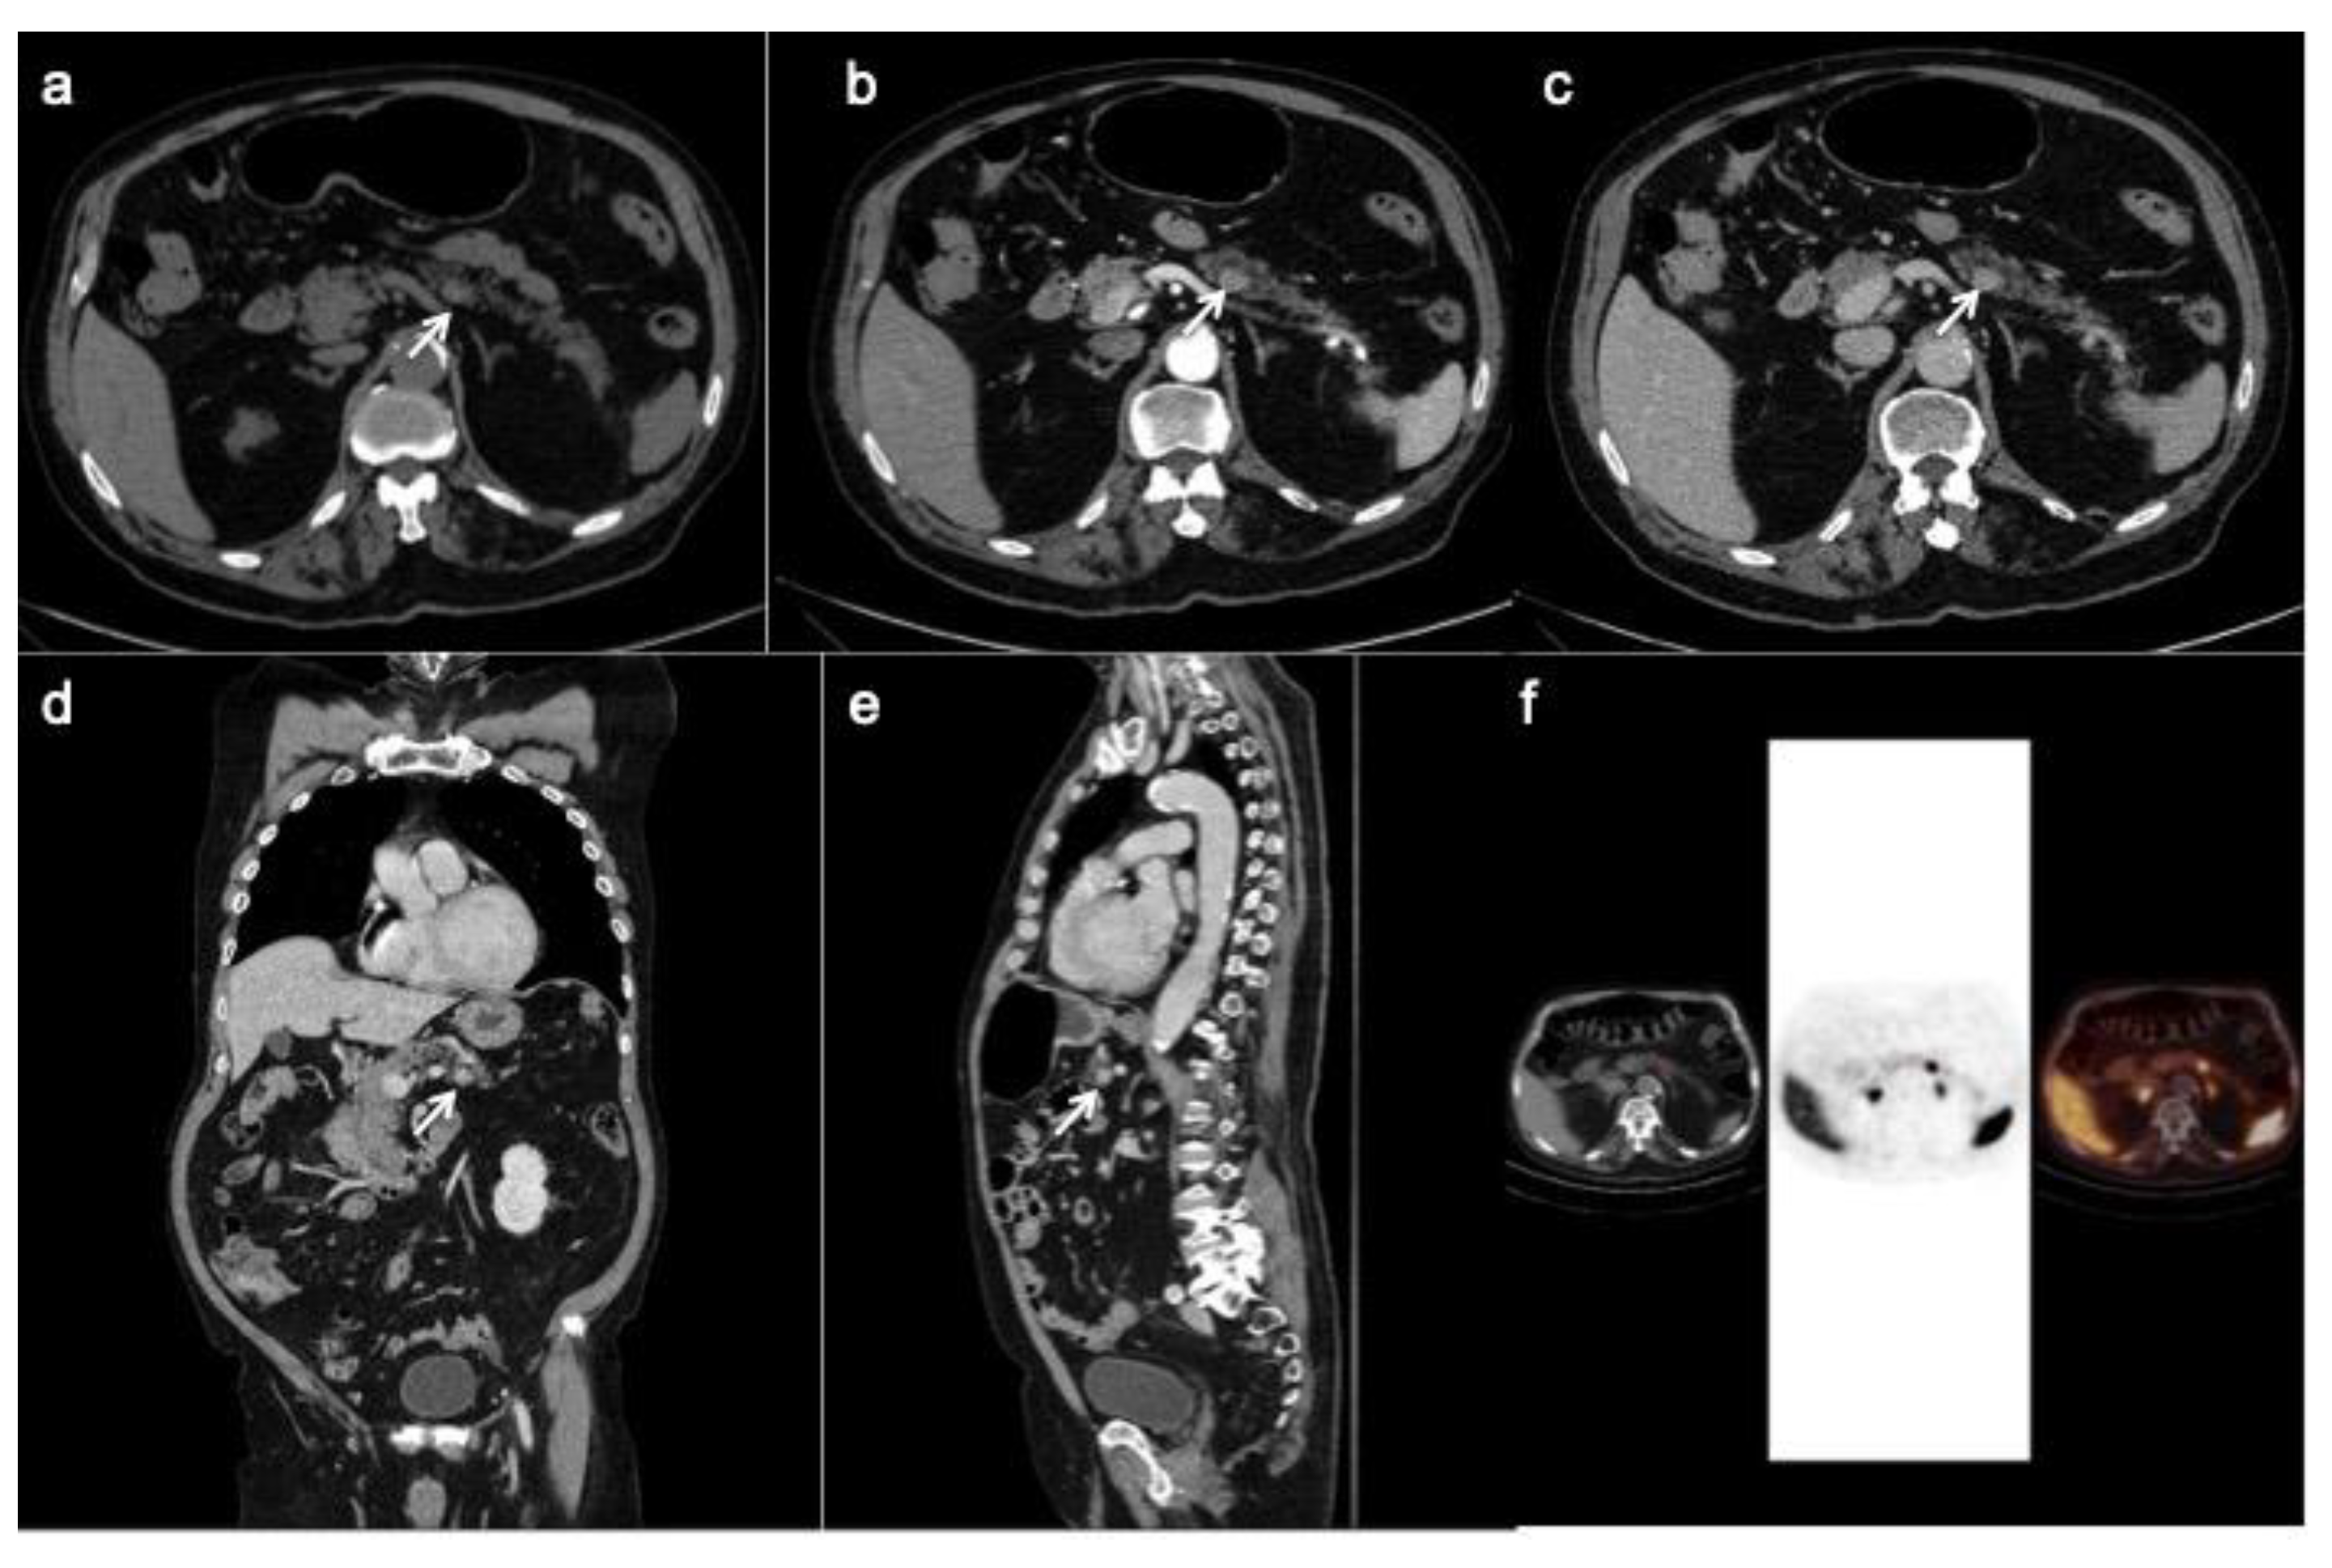

PET/CT with 68-Gallio labeled SSA is the imaging method of choice for panNEN functional study. There are mainly three available SSAs showing no substantial differences in patients staging: 68-Ga-DOTANOC, 68-Ga-DOTATOC (Figure 5) and 68-Ga-DOTATATE. All of them are SSRT2 high-affinity tracers; only 68-Ga-DOTANOC proved to have an affinity for SSRT3.

Figure 5.

CT images (a–c) show a hyper-enhancing pancreatic nodule in the body/tail of the organ (arrows) well depicted on the coronal (d) and sagittal (e) reconstruction too. The 68-Ga-DOTATOC PET/CT (f) shows focal uptake in the pancreatic lesion.

Compared to SRS, PET/CT has shown higher sensitivity and specificity for identifying receptor-positive panNENs [66]. Several studies on the diagnostic accuracy of 68-GaSSTA PET in gepNENs have demonstrated a sensitivity range of 88–93%, and specificity range of 88–95% [21]. PET/CT and CT should be considered as complimentary procedures for patients with a suspected panNEN. Indeed, Versari et al. calculated a CT sensitivity of 91% and a mean 92% with 68-Ga DOTA-TOC for detection of duodeno-pancreatic neoplasia [67].

Furthermore, this nuclear technique has other advantages: the study has a lower radiation dose for the patient, thanks to the 2 h protocol, in comparison to 24 h of SRS; 68-GA SSA tracers have a favorable normal biodistribution, with a lower liver up-take, which can increase metastasis detection rate; background physiological uptake is similar to Octreoscan, with prominent uptake in adrenal glands and in the uncinated process of the pancreas, so that can be misdiagnosed as panNEN [68]. Standardized uptake values (SUVs) are calculated for quantitative analysis, allowing a direct comparison among exams performed with the same radiotracer.

PET/CT plays a crucial role in metastasis detection, especially bone ones, when CT is negative or ambiguous. In a study by Prasad et al., 68-Ga-DOTANOC PET helped identify lymph node involvement in all patients, whereas CT identified nodal involvement in only 50% of patients [72].